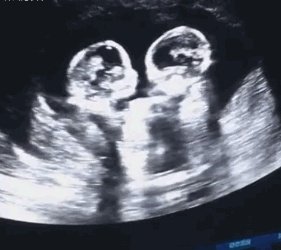

那天看到宁夏双胞胎在肚子里打架的视频,感觉特别可爱,这对双胞胎已经平安出生,

具体是这样的,一个怀有双胞胎的孕妇去做产检时,发现两个孩子在打架,你一拳我一拳,推推搡搡,嘴里好像念念有词,战斗了几个回合不停止,把在场的人引得哈哈大笑。

之前网上面曾经看到过这样的一组动图,是双胞胎妈妈的B超影像。只见两个宝宝在一起,其中一个宝宝很是活跃,对着另外一个宝宝,一会动一下手,一会动一下脚的。从外面看起来就像是两个宝宝在打架一样。